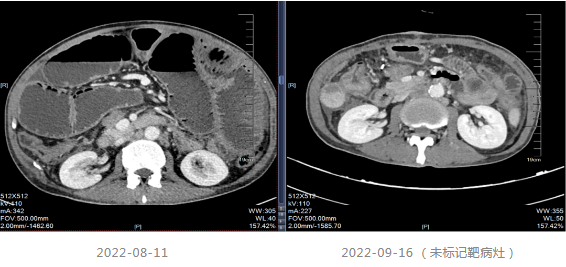

2021.06-01复查影像学提示肝胃间隙及腹膜后淋巴结较前增大,疗效评价PD。

2021-06-08至2021-12-11采用“贝伐珠单抗+Cap”治疗8个周期。

2021-12-15影像学复查提示疾病进展。